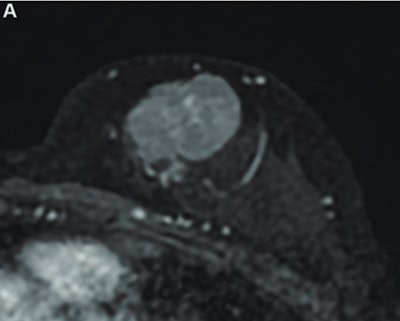

MR image from a 55-year-old patient with triple-negative breast cancer from training set. (A, above) Axial postcontrast T1-weighted image from baseline MRI exam shows unifocal enhancing mass (unifocality: positive). (B, below) Axial postcontrast T1-weighted image from MRI examination per-formed after one cycle of neoadjuvant chemoimmunotherapy shows >37% reduction in lesion size (early tumor shrinkage: positive) and development of non-enhancing region within lesion (percentage enhancement reduction: positive).ARRS

The researchers reported the following independent predictors of complete pathologic response in the training set: tumor unifocality (odds ratio [OR] = 7.2, p = 0.001) on pretreatment MRI, early tumor shrinkage ≥ 37% (OR = 9.7, p < 0.001), and percentage enhancement reduction (OR = 9.7, p < 0.001) on early-chemotherapy MRI.